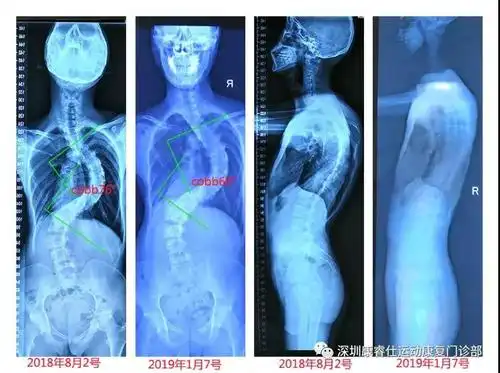

分享一个76度脊柱侧弯改善案例希望可以帮到有需要的朋友